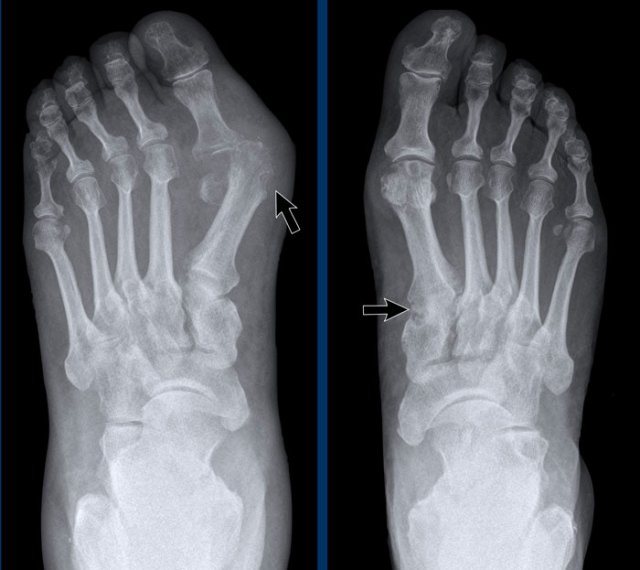

Rheumatoid arthritis in the feet Rheumatoid arthritis in the feet

In this case of rheumatoid arthritis there are marginal erosions adjacent to almost all MTP joints (arrowheads).

The 5th MTP joint is most frequently involved in  rheumatoid arthritis.

When erosions are as severe as in this case, it can look like pencil-in-cup deformity (white arrow) as is frequently seen in psoriatic arthritis.

However, the primarily affected MTP joints distribution and less affected interphalangeal joints is the clue that this is a case of rheumatoid arthritis.